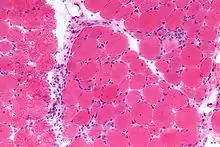

- Examining a muscle biopsy under a microscope and finding mononuclear white blood cells between the muscle cells, and finding abnormal muscle cell degeneration and regeneration, dying muscle cells, and muscle cells being consumed by other cells (phagocytosis)